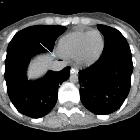

Systemic air

embolism and decompression illnes in a scuba diver.. Arrow shows gas in left innominate vein.